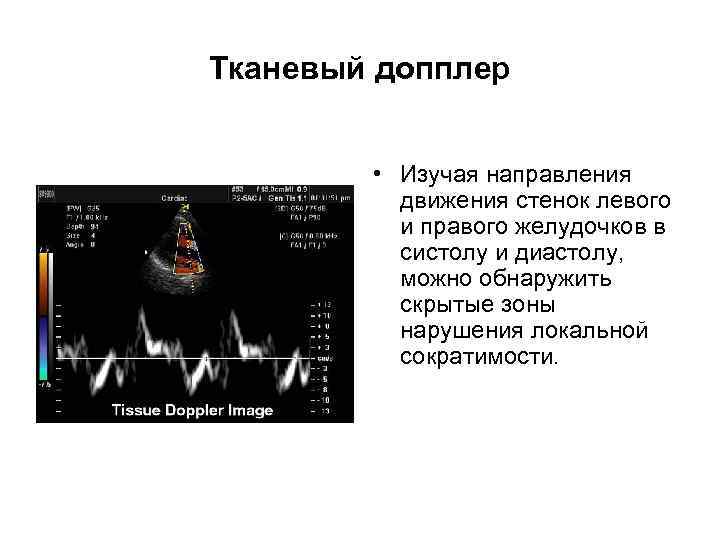

Тканевый допплер • Изучая направления движения стенок левого и правого желудочков в систолу и диастолу, можно обнаружить скрытые зоны нарушения локальной сократимости.

Тканевый допплер • Изучая направления движения стенок левого и правого желудочков в систолу и диастолу, можно обнаружить скрытые зоны нарушения локальной сократимости.